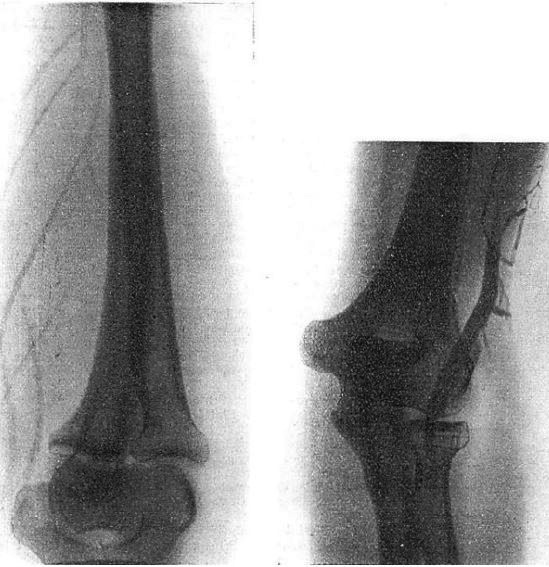

初の経大腿動脈法による腹部血管造影を報告した論文.鼠径部で大腿動脈を露出し,太い針(トロカール)で穿刺して尿管カテーテルを挿入し,ジオドラストを注入して大動脈造影を行なっている.検査後は動脈外膜を縫合,閉創する.まだ外科的侵襲は大きいとはいえ,大動脈の盲目的直接穿刺にくらべればかなり安全になったといえる.